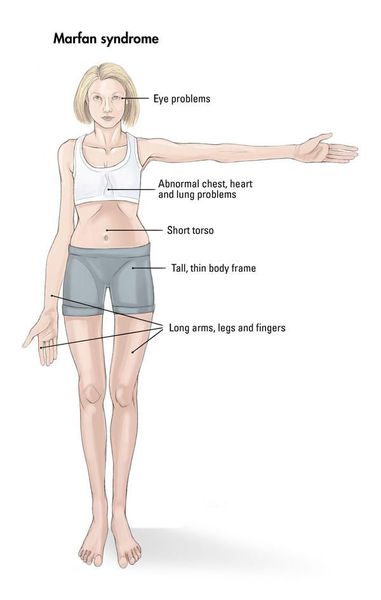

Boleznennyj dar nikkolo paganini redkij sindrom marfana priznaki sposoby lecheniya i nasledovanie u detej sindrom marfana kto bolel iz znamenitostej (Тип файлу jpg)

Boleznennyj Dar Nikkolo Paganini Redkij Sindrom Marfana Priznaki Sposoby Lecheniya I Nasledovanie U Detej Sindrom Marfana Kto Bolel Iz Znamenitostej

Chelovek i ego zdorove sindrom marfana sekrety andersena paganini i chukovskogo obsuzhdenie na liveinternet rossijskij servis onlajn dnevnikov (Тип файлу jpg)

Chelovek I Ego Zdorove Sindrom Marfana Sekrety Andersena Paganini I Chukovskogo Obsuzhdenie Na Liveinternet Rossijskij Servis Onlajn Dnevnikov